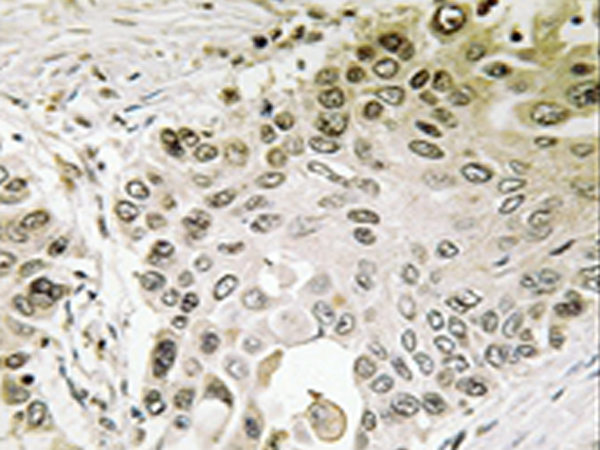

IHC |

IHC positive control: |

Human lung carcinoma tissue |

IHC Recommend dilution: |

50-100 |